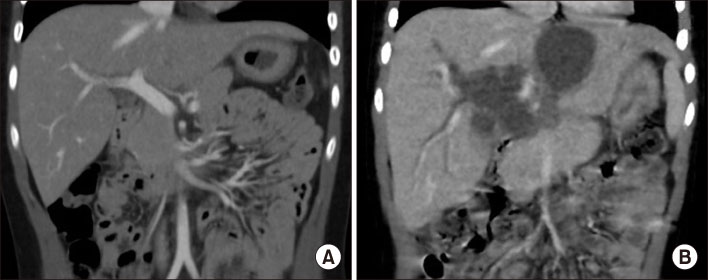

Fig. 5

Fig. 5 Linear capsular fibrotic change on the left 3 cm from the falciform ligament (arrows).